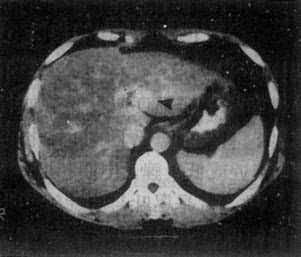

图4-3-6 肝癌(MRI)

A、T1WI肝右叶可见大块较低信号区,其内信号不均,轮廓不规

则(↓)。门静脉内可见相同信号强度影像,为癌栓所致(↓)

B、T2WI上述稍低信号区成为稍高信号区(↓),门静脉内癌栓的信

号也增强(↓)